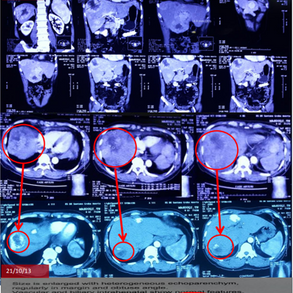

Stage 4 Metastatic Breast Cancer with Acute Liver Failure